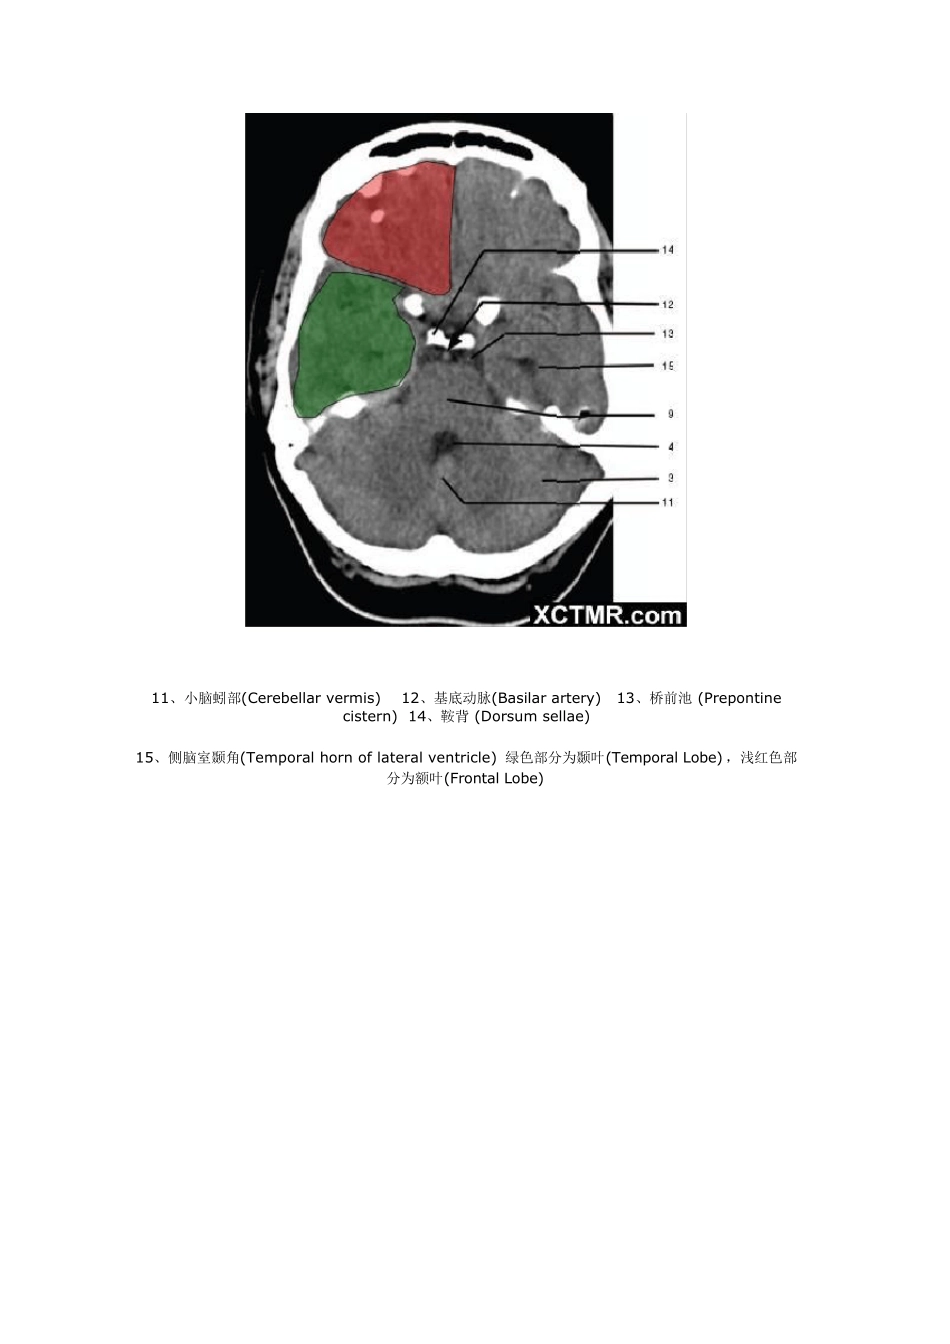

颅脑CT 解剖(图文) 1、蝶窦(Sphenoid sinu s) 2、延髓 (Medu lla oblongata) 3、小脑 (cerebellu m) 绿色部分为颞叶(Temporal Lobe),浅红色部分为额叶(Frontal Lobe) 4、第四脑室(Fourth ventricle) 5、小脑中角(Middle cerebellar peduncle) 6、乙状窦(Sigmoid sinus) 7、颞骨及乳突气房 (Petrous temporal bone and mastoid air cells) 8、桥小脑角(Cerebellopontine angle) 9、脑桥 (Pons) 10、垂体窝(Pituitary fossa) 绿色部分为颞叶(Temporal Lobe),浅红色部分为额叶(Frontal Lobe) 11、小脑蚓部(Cerebellar vermis) 12、基底动脉(Basilar artery) 13、桥前池 (Prepontine cistern) 14、鞍背 (Dorsum sellae) 15、侧脑室颞角(Temporal horn of lateral ventricle) 绿色部分为颞叶(Temporal Lobe) ,浅红色部分为额叶(Frontal Lobe) 16、环池 (Ambient cistern) 17、角间池 (Interpeduncular cistern) 18、大脑角 (Cerebral peduncle) 19、侧裂池 (Sylvian fissure) 绿色部分为颞叶(Temporal Lobe),浅红色部分为额叶(Frontal Lobe) 20、小脑上池 (Third v entricle) 21、侧脑室前角 (Frontal horn of lateral v entricle) 21a、第三脑室 (Third v entricle) 绿色部分为颞叶(Temporal Lobe),浅红色部分为额叶(Frontal Lobe),黄色部分为枕叶(Occipital Lobe) 22、尾状核头部 (Head of caudate nucleus) 23、岛叶 (Insular cortex) 24、外囊 (External capsule) 25、豆状核(Lentiform nucleus) 26、丘脑(Thalamus) 绿色部分为颞叶(Temporal Lobe),浅红色部分为额叶(Frontal Lobe),黄色部分为枕叶(Occipital Lobe) 27、纵裂 (Interhemispheric fissure) 28、内囊前肢 (Anterior limb of internal capsule) 29、内囊膝部 (Genu of internal capsule) 30、内囊后肢(Posterior limb of internal capsule) 31、侧脑室三角区及脉络丛钙化(Trigone of lateral ventricle and calcified choroid plexus) 32、侧脑室枕角(Occipital horn of lateral ventricle) 绿色部分为颞叶(Temporal Lobe),浅红色部分为额叶(Frontal Lobe),黄色部分为枕叶(Occipital Lobe),褐色部分为顶叶(Parietal Lobe) 33、侧脑室体部 (Body of lateral ventricle) 34、放射冠 (Corona radiata) 浅红色部分为额叶(Frontal Lobe),黄色部分为枕叶(Occipital Lobe),褐色部分为顶叶(Parietal Lobe) 35、半卵圆中心 (Centrum semiovale) 浅红色部分为额叶(Frontal Lobe),黄色部分为枕叶(Occipital Lobe), 褐色部分为顶叶(Parietal Lobe) 额骨(FB— Frontal bone) 顶骨(PB — Parietal bone) 枕骨(OB— Occipital bone) 36、中央前回 (Pre-central gyrus) 37、中央沟(Central sulcus ) 38、中央后回 (Post-central gyrus) 浅红色部分为额叶(Frontal Lobe),褐色部分为顶叶(Parietal Lobe) 浅红色部分为额叶(Frontal Lobe),褐色部分为顶叶(Parietal Lobe) 浅红色部分为额叶(Frontal Lobe),褐色部分为顶叶(Parietal Lobe)